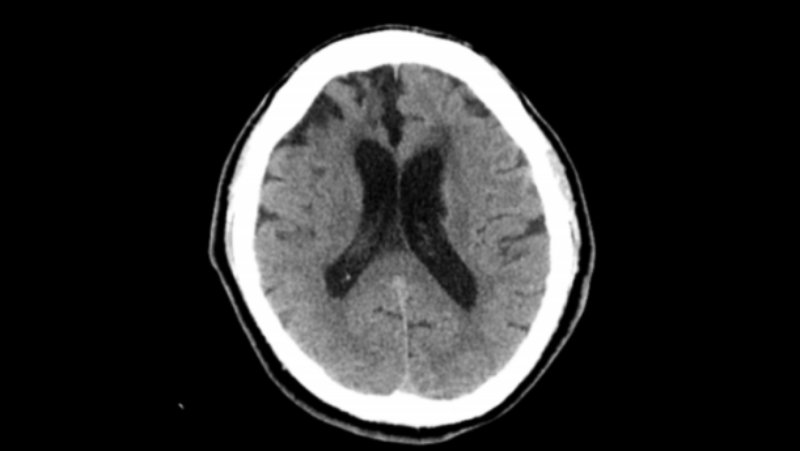

47 歲的張濤(化名)在工作的時候突然就失去意識,隨即撥打 120。來到惠州市中心人民醫(yī)院博羅分院(博羅縣人民醫(yī)院)急診醫(yī)學科,醫(yī)生給他接上呼吸機并進行了止血、補液等緊急處理,后經(jīng)查CT ,結(jié)果顯示是“丘腦出血”,而且還有血流進了腦室里,有腦積水的情況。經(jīng)醫(yī)生診斷為左側(cè)丘腦出血并破入腦室以及梗阻性腦積水。因為患者出血量比較大,還引起了腦積水,必須趕快想辦法把這個梗阻解除,不然容易出現(xiàn)腦疝?;葜菔兄行娜嗣襻t(yī)院派駐博羅分院主任醫(yī)師、博羅分院腦外科中心主任羅洪海帶領團隊迅速組織討論后,決定使用軟通道技術(shù)來處理是最合適的治療策略。于是神經(jīng)外科副主任戴兵和家屬溝通商量治療策略后,在床邊局麻下用軟通道技術(shù)為患者進行“雙側(cè)腦室錐顱置管引流術(shù)”。

入院CT-1